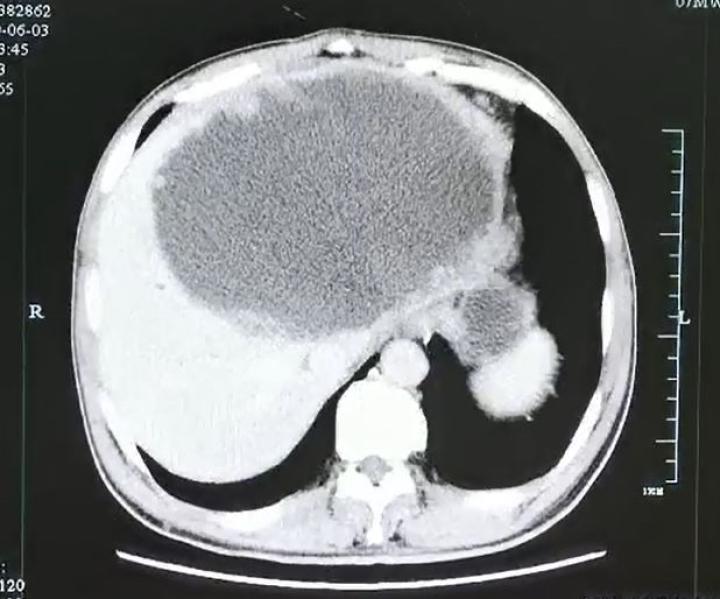

入院后腹部CT检查发现肝脓肿壁上长了很多肿瘤样的结构,而且壁很厚。看来这个肝脓肿不简单。

为了让脓球变小,进一步追查“元凶”,医生在超声指引下给谢师傅做了脓球的穿刺引流。结果大量的灰白色脓液被顺利引出,但是经过一系列的检查后,却没有发现细菌、真菌、结核和恶性肿瘤的“踪迹”。那谢师傅到底得了什么病呢?

经过肝胆外科、感染科、影像科等多学科会诊及讨论后,贾长库主任、沈伟敏主任医师、徐孙兵副主任医师等,果断地为患者进行了手术将左半肝切除,完整地拿掉了这个迷雾重重的病灶。

谁都没有想到,病理显示脓肿壁上大量的肿瘤样结构竟然是肉芽肿性炎性肿块,里面甚至还爬满了灯泡状、壳厚的华支睾吸虫虫卵,脓肿内多得数不清,看得人头皮发麻。